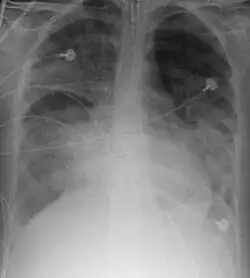

![]() | |

| Relação entre a pressão parcial de oxigênio em sangue (pO2) e a saturação das hemoglobinas com oxigênio (sO2%). O valor normal de sO2 é maior que 95% em sangue arterial e valores menores a 90% indicam insuficiência respiratória. | |